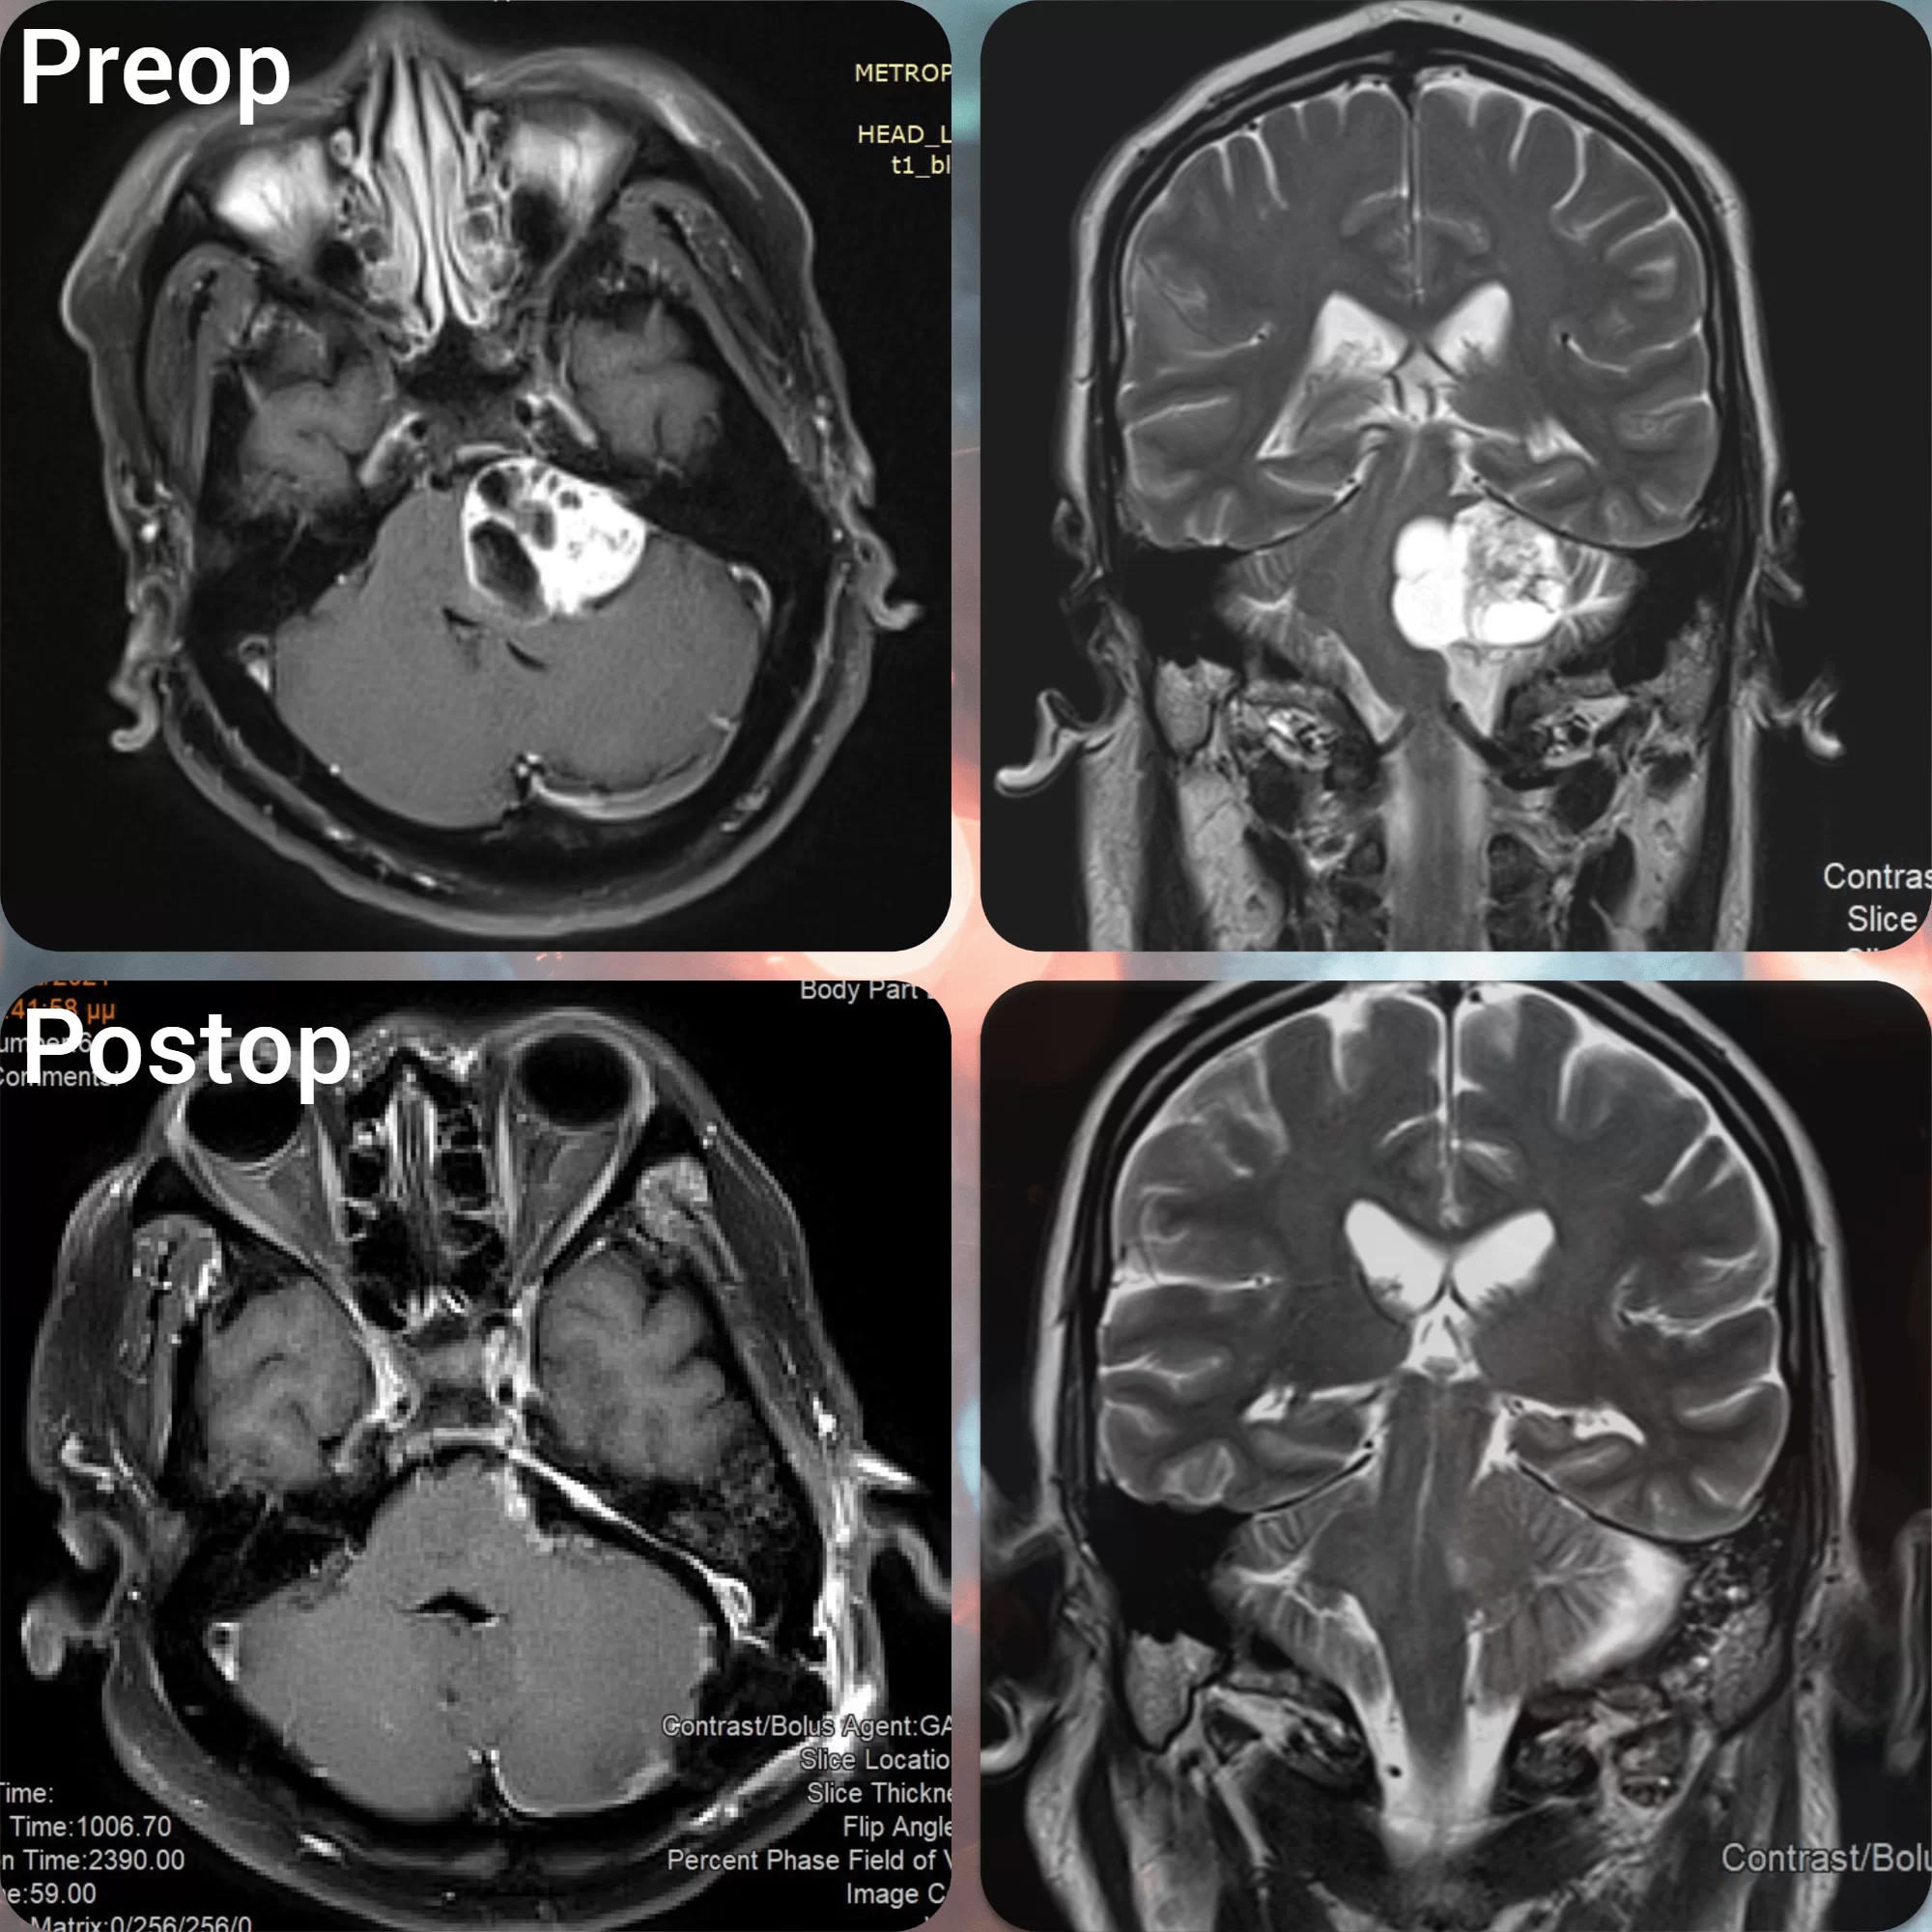

- Απεικονιστικές εξετάσεις, όπως μαγνητική τομογραφία ή αξονική τομογραφία – Η μαγνητική τομογραφία είναι η εξέταση εκλογής για τη διάγνωση των ακουστικών νευρινωμάτων (εικόνα 1). Η μαγνητική θα δείξει αν υπάρχει πράγματι ακουστικό νευρίνωμα, ποιό είναι το μέγεθός του, που ακριβώς εντοπίζεται, αν πιέζει κλπ. Η αξονική τομογραφία είναι συμπληρωματική της μαγνητικής.

- Χειρουργική επέμβαση – Στόχος της χειρουργικής αφαίρεσης είναι η πλήρης ή σχεδόν πλήρης αφαίρεση του όγκου. Σε μικρά νευρινώματα, όπου υπάρχει ακόμα ακοή, είναι δυνατόν να διατηρηθεί η ακοή, ενώ αν ο ασθενής έχει χάσει την ακοή του, αυτή δεν θα επανέλθει με το χειρουργείο.

- Παρακολούθηση – Αυτό σημαίνει ότι δεν γίνεται κάποια θεραπεία, αλλά ο ασθενείς παρακολουθείται ανά τακτά χρονικά διαστήματα, προκειμένω να διαπιστωθεί άν ο όγκος μεγαλώνει ή αν τα συμπτώματα αλλάζουν. Αυτό γίνεται με μαγνητική τομογραφία και ακουολογικές εξετάσεις, συνήθως μια φορά το χρόνο. Άν το ακουστικό νευρίνωμα μεγαλώσει ή προκαλέσει συμπτώματα, τότε μπορεί να αποφασιστεί θεραπεία.

Παρόλο που τα ακουστικά νευρινώματα είναι καλοήθεις όγκοι, υπάρχει ο κίνδυνος να επανεμφανιστούν. Ο κίνδυνος αυτός είναι πολύ μικρός όταν η αφαίρεση είναι ολική.

Αν ένα ακουστικό νευρίνωμα παρακολουθείται απλώς ή αν πρόκειται για έλεγχο μετά απο χειρουργείο, τότε ο πρώτος έλεγχος γίνεται στο εξάμηνο και μετά συνήθως ανα έτος. Τα χρονικά διαστήματα μπορούν να αυξηθούν στην πορεία. Αν ο όγκος παραμένει σταθερός για μια δεκαετία περίπου, τότε δε χρειάζεται περαιτέρω παρακολούθηση αλλά αυτό εξαρτάται απο διαφόρους παράγοντες όπως η ηλικία.